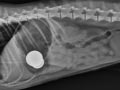

Diagnosa penyakit :

• Dilihat dari sejarah penyakit dan gejala klinis yang muncul

• Pemeriksaan laboratorium (pemeriksaan darah, pemeriksaan analisis urin, pemeriksaan preparat apus darah). Pada anjing penderita toxoplasmosis terjadi pada pemeriksaan analisis darah terjadi leukopenia, neutropenia, lymphopenia sedangkan pada pemeriksaan analisis urin terjadi peningkatan kadar protein dan bilirubin

• Pemeriksaan biokimia, terjadinya abnormalitas tingginya enzim ALT dan AST pada hati

• Serological test untuk mengetahui kadar IgM dan IgG

• PCR (Polymerase Chain Reaction)

• CSF (Cerebrospinal Fluid)